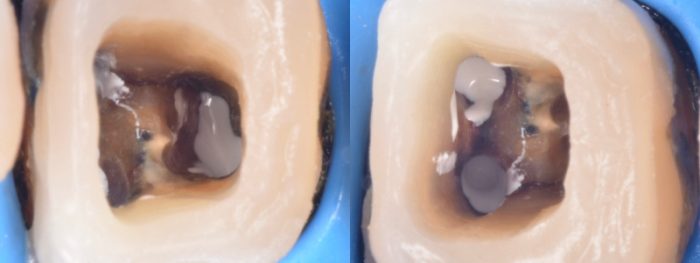

青いシートが歯ぐきや舌をカバーしています。

これで治療中に唾液が歯の中に入ることを防ぎ、細菌の巻き込みを防止することができます。

また、細菌の侵入は、唾液からだけではなく、唇や頬、舌の粘膜からも起こります。

ラバーダム防湿はそれらも防いでくれます。

この日は、根管内の感染物をマイクロスコープで見ながら除去し、消毒してから、

内部に消毒薬(白いクリーム)を入れ、

その後、

蓋をして、さらに全体の形を整えました。

この後、ここに仮歯が入り、終了です。